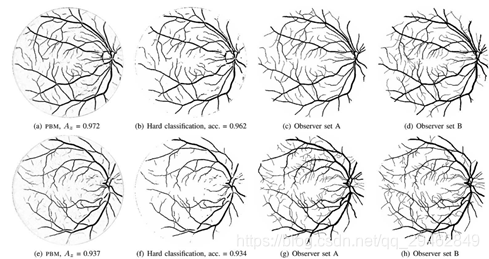

六、用于视网膜提取的数字视网膜图像

数据下载链接:https://www.isi.uu.nl/Research/Databases/DRIVE/download.php

数据介绍:用于视网膜图像中血管分割的比较研究,它由40张照片组成,其中7张显示出轻度早期糖尿病性视网膜病变的迹象。

用于血管提取的数字视网膜图像(DRIVE)

DRIVE数据库用于对视网膜图像中的血管分割进行比较研究。它由40张照片组成,其中7张显示轻度早期糖尿病视网膜病变的迹象。

论文:https://ieeexplore.ieee.org/document/1282003

访问:http://www.isi.uu.nl/Research/Databases/DRIVE/download.php

https://drive.grand-challenge.org/DRIVE/